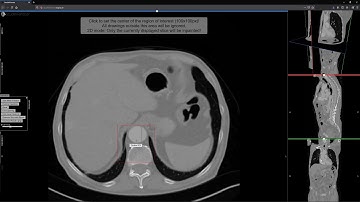

Semi-supervised Virtual Regression of Aortic Dissections Using 3D Generative Inpainting (Talk)